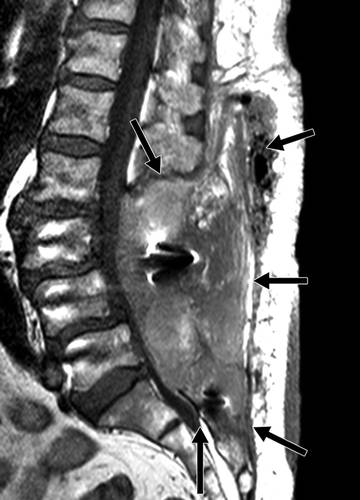

图4A-76岁女性,背痛和严重退行性变,行腰椎融合,椎板切除术后8天。矢状T1加权MR图像显示从L2到S1的椎板切除部位的大的异常信号(箭头),延伸到硬膜外间隙,致硬膜囊受压和椎管狭窄。